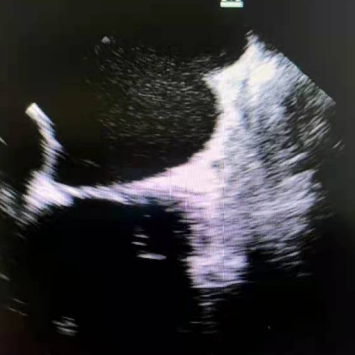

2021年8月28日上午10点,手术正式开始。食管彩超显示左心耳无血栓,李耀东教授带领奎屯医院心内科王飞、杨鸿英、张娟医生进行房间隔穿刺,左心耳造影结果显示为鸡翅型左心耳,在测量左心耳开口宽度和深度后,确定锚定区与封堵区,李教授选择了LAmbre™ 2430封堵器,经输送鞘管送至左心耳实现封堵。造影及食道超声显示均无残余分流,牵拉测试稳定,符合COST原则,释放后取得了理想的封堵效果。随后李耀东教授带领团队对患者4条肺静脉进行冷冻消融,手术历时2小时顺利成功,术后第二日患者活动正常,身体恢复良好。

2021年9月12日中午13时许,左心耳封堵术正式开始。首先唐琪老师在TEE下,排除了心房室结构及左心耳内血栓存在的风险,同时在多角度下对左心耳封堵器的锚定区和开口区进行了测量。随后在李耀东教授及王继伟副院长的带领下行房间隔穿刺,房穿后鞘管轴向极佳,即刻对左心耳进行了造影,结果显示左心耳形态呈鸡翅菜花型,测量后锚定区24mm,封堵区32mm,综合评估后选用LAmbre™ 2834封堵器进行封堵。DSA和TEE下显示无残余分流,牵拉稳定,完美封堵,整个手术用时仅40余分钟。